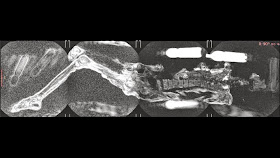

Scans of the dislocated right hip, with bright red color marking edematous tissue in right inguinal area

[Credit: Alexander Tyryshkin, Dr Andrey Letyagin]

We see the traces of traumas she got not so long before her death, serious traumas - dislocations of joints, fractures of the skull.

These injuries look like she got them falling from a height.'

'In such a condition, she could fall from her horse and suffer serious injuries. She obviously fell on her right side, hit the right temple, right shoulder and right hip.

Her right hand was not hurt, because it was pressed to the body, probably by this time the hand was already inactive.

Though she was alive after her fall, because edemas are seen, which developed due to injuries.